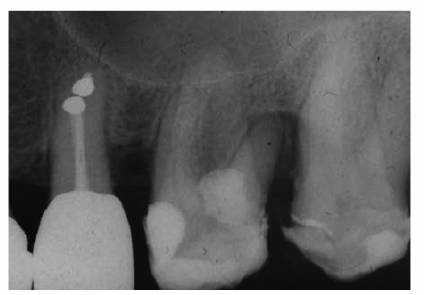

One can suspect a necrotic pulp if the reading is negative. Endodontics would

then be the treatment of choice (Figures 19-17A, and 19-17B). If the reading is positive and

there are no pulpal symptoms, periodontal therapy would be indicated (Figures 19-17C 19-17D, and 19-17E). Endodontic treatment may be

required if the root apices are compromised during periodontal procedures (Figures 19-17F, and 19-17G

Figure 19-17A: Mandibular molar with a necrotic pulp. Root canal therapy was instituted.

Figure 19-17B: Ten years following completion of root canal therapy there is a complete bone fill-in. No periodontal treatments were performed on this tooth.

Figure 19-17C: Maxillary central incisor tooth with a vital pulp. Endodontic therapy was not indicated.

Figure 19-17D: A maxillary first molar with a periapical radiolucency.

Figure 19-17E: A gutta-percha point placed in the distal pocket. Pulp testing through an occlusal opening revealed a vital pulp. The cause of the radiolucency was of periodontal origin and therapy followed that course.

Figure 19-17F: Maxillary first molar with an uninflamed vital pulp. There was extensive bone loss surrounding the distobuccal root.

Figure 19-17G: Root canal therapy was performed to allow for the resection of the periodontally involved root.